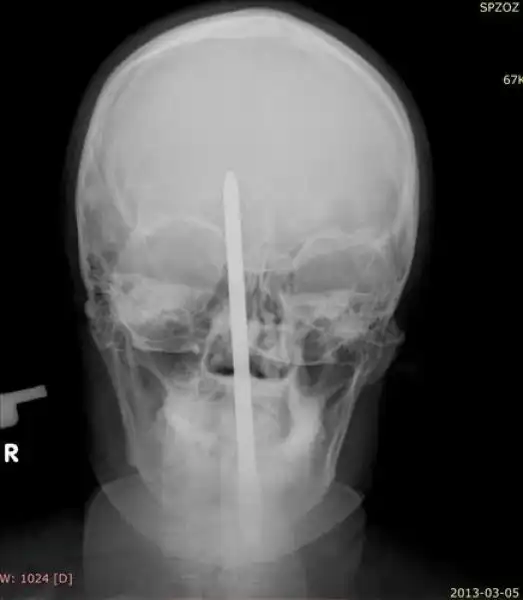

Мужик вогнал себе в мозг отвертку, закурил и отправился в больницу

25-летний поляк трудился у себя в саду, когда потерял равновесие и упал на инструменты. Поднявшись и придя в себя он посмотрел в зеркало и обнаружил, что у него из головы торчит отвертка. Мужик не стал суетиться, а просто достал сигарету, закурил и отправился к соседу, чтобы тот помог ему добраться до больницы. Как оказалось, отвертка вошла в мозг на пять сантиметров, но очень удачно, поэтому инструмент без труда извлекли, а дырку залатали.